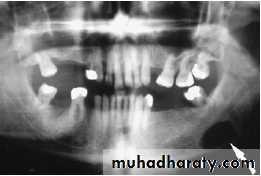

80% submandibular stones are radio-opaque

sialogram